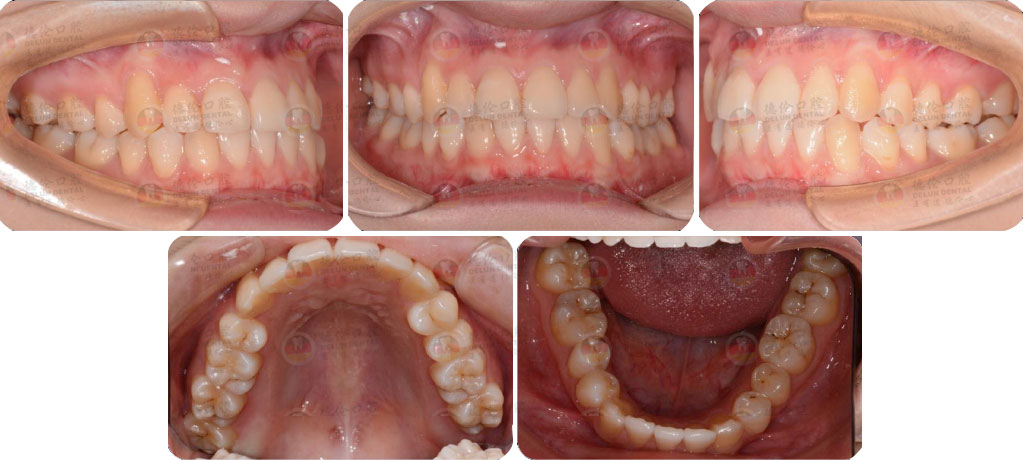

矯治采用兩種不同的厚度的膜片(牙套),發揮兩種不同膜片的各自優勢,在有效的作用時間內,矯治效率、矯治目標達成和舒適度方面較普通隱形矯正方式有明顯提升。

Angelalign Pro 3大技術支撐5大優勢

- 可預知

結合3D數字化口掃技術,可親自見證矯正后模擬效果圖

- 更美觀

MasterControl™材料,入射光會在材料表面形成漫反射,矯治器更隱形、美觀

- 更高效

在保證矯正效果的情況下,大幅度縮短矯正時間

- 更準確

厚薄兩種矯治器,每周替換有利于牙齒位置的準確控制

- 更舒適 在不影響牙齒移動速度的前提下讓患者舒適度大大提高